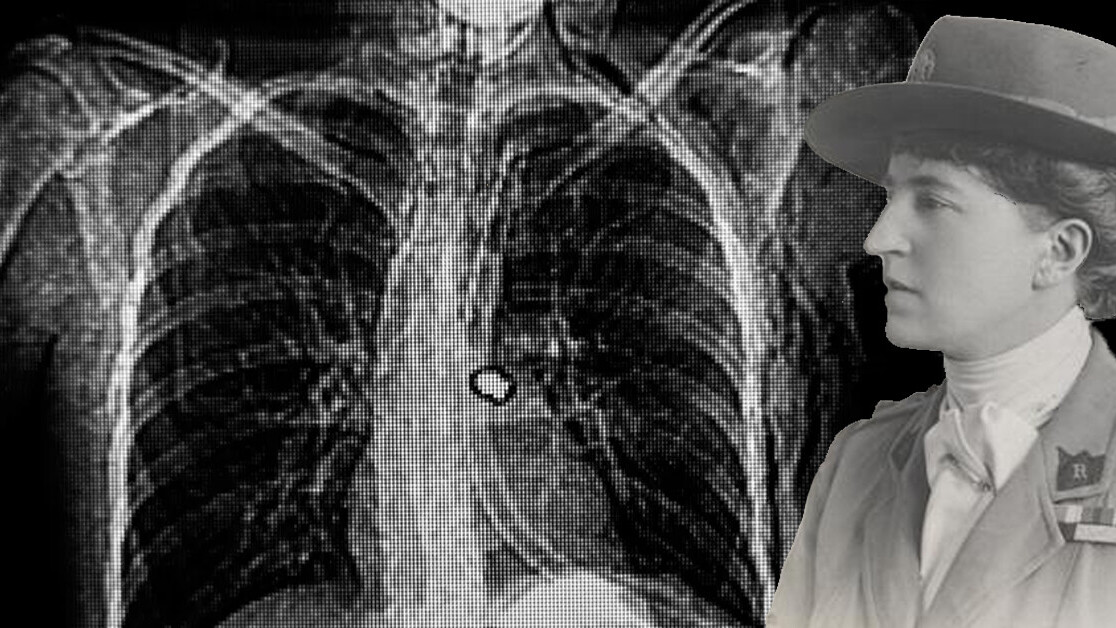

Although photos show two demure women in heavy uniforms, hats firmly in place even when working inside, Gleichen recounts adventures as hair-raising as those of any frontline soldier. Often at risk from enemy bullets, they took many thousands of X-rays, eventually damaging their hands and their eyes.

In a letter to Davidson, Gleichen explained that they needed to work quickly. With more and more wounded soldiers arriving daily, many of them already close to death, there was often no time for the luxury of standard procedures. Weighing down their un-anesthetized patients with sandbags, they explored precisely yet rapidly to locate bullets lodged in a soldier’s body by a rough-and-ready technique of aiming along two perpendicular lines to see where they intersected.

Gleichen was particularly jubilant about managing to pinpoint a bullet deep inside a soldier’s skull. She sent Davidson a small sketch, telling him that she was “cocka hoopy”. Despite this experimental success, she faced up to wartime realities: “Anyway it has been deeply interesting + I expect they will kill him by operating + equally kill him by leaving it. I am sorry as he was such a nice boy in tremendous spirits + health.”